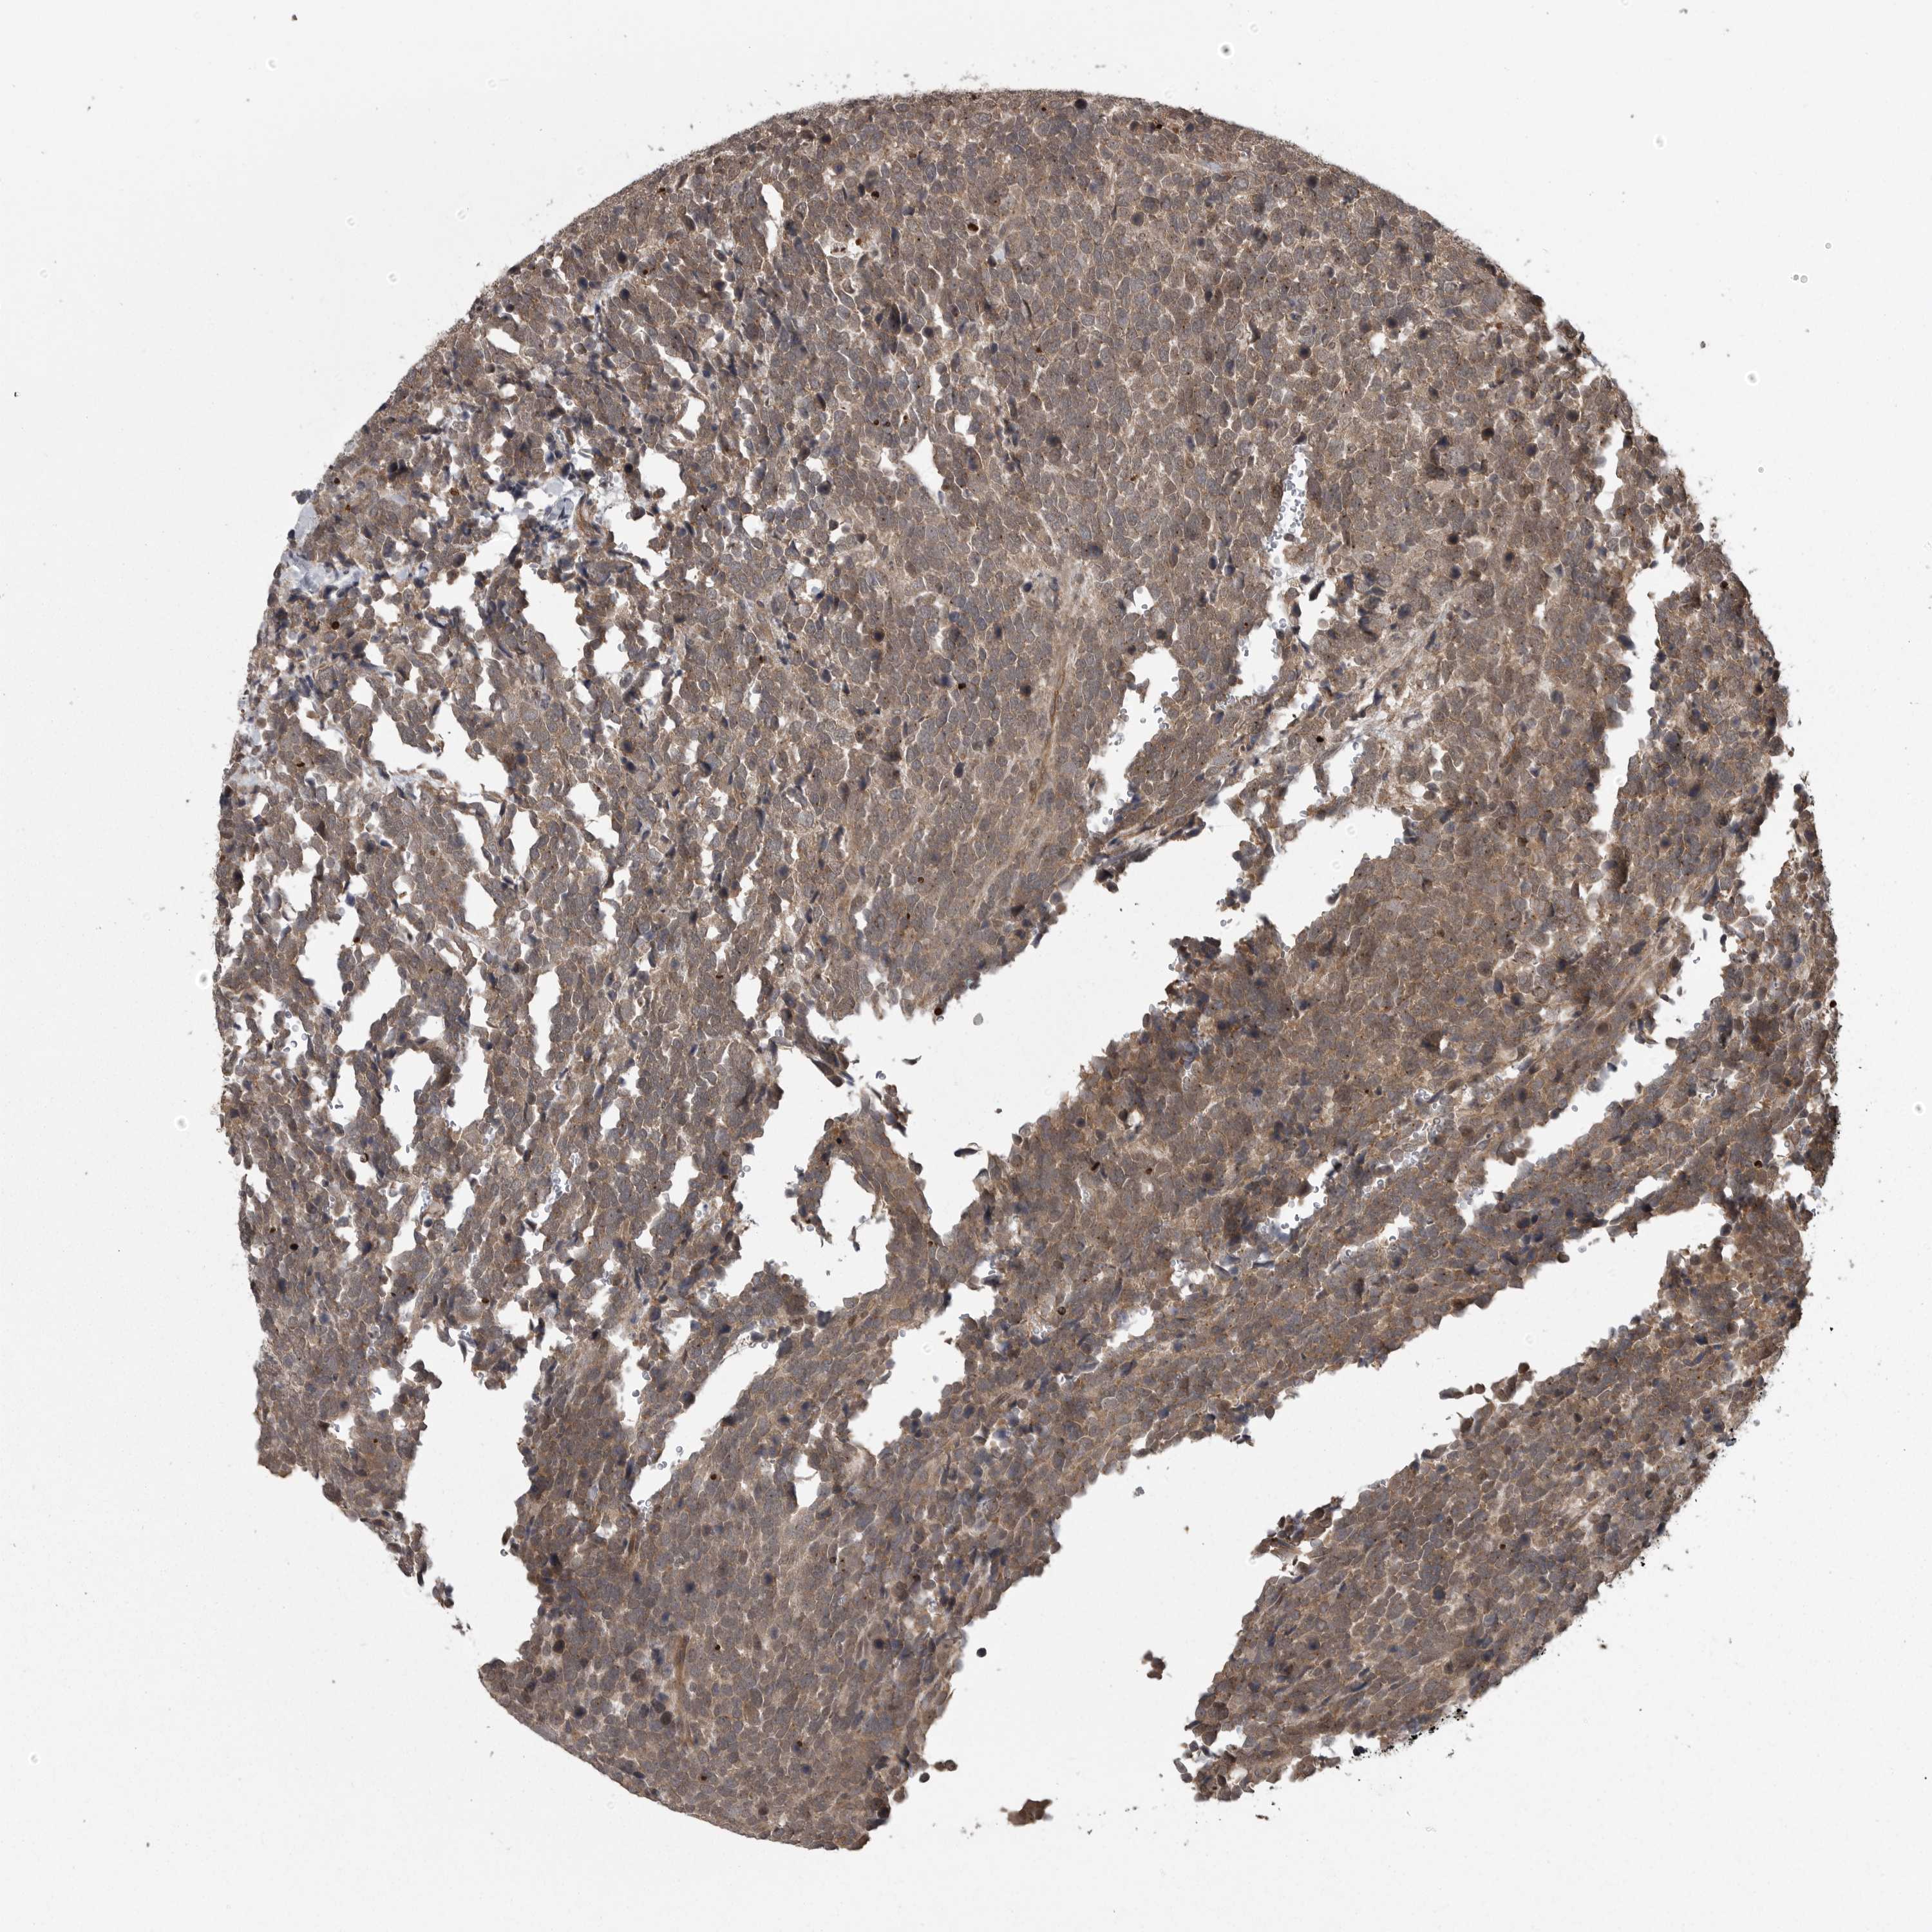

UROTHELIAL CANCER - Protein expressioni

A mouse-over function shows sample information and annotation data. Click on an image to view it in a full screen mode. Samples can be filtered based on level of antibody staining by selecting one or several of the following categories: high, medium, low and not detected. The assay and annotation is described here.

Note that samples used for immunohistochemistry by the Human Protein Atlas do not correspond to samples in the TCGA dataset.

Antibody stainingi

Antibody staining in the annotated cell types in the current human tissue is reported as not detected, low, medium, or high, based on conventional immunohistochemistry profiling in selected tissues. This score is based on the combination of the staining intensity and fraction of stained cells.

Each image is clickable and will lead to virtual microscopy that enables deeper exploration of all samples and also displays staining intensity scores, fraction scores and subcellular localization as well as patient and tissue information for each sample.

Antibody HPA026283

Staining

High

Medium

Low

Not detected

Intensity

Strong

Moderate

Weak

Negative

Quantity

>75%

75%-25%

<25%

None

Location

Nuclear

Cytoplasmic/membranous

Cytoplasmic/membranous,nuclear

Urothelial carcinoma, Low grade

Urothelial carcinoma, High grade